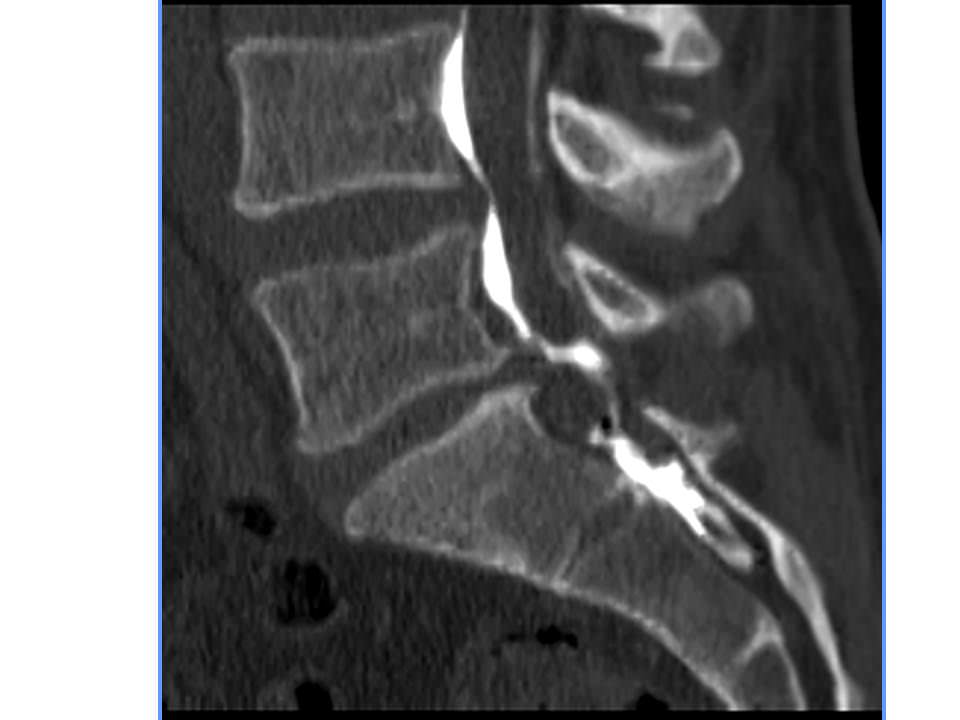

Les infiltrations concernent souvent les étages L4-L5 et L5-S1 à cause de la prévalence importante des sciatalgies par rapport aux autres types de douleurs nerveuses Les témoignages des patients peuvent jouer un rôle crucial dans la perception de cette procédure médicale

Epidurale Infiltrationen bei Rückenschmerzen Orthopaedie Schmerztherapie. De nombreux individus partagent leur expérience sur des plateformes en ligne, ce qui a pour effet d'influencer les opinions d'autres personnes confrontées à des douleurs lombaires persistant malgré. Je viens de subir une infiltration épidurale L4 L5 en raison d'une sciatique dont l'origine semble être un canal lombaire étroit combiné à une antélisthésis de L4 sur L5.

Infiltration épidurale La Radiologie. Notre article explore les opinions des patients et des professionnels de santé pour vous aider à mieux comprendre cette procédure médicale, ses avantages, ses inconvénients et les résultats attendus Les infiltrations concernent souvent les étages L4-L5 et L5-S1 à cause de la prévalence importante des sciatalgies par rapport aux autres types de douleurs nerveuses